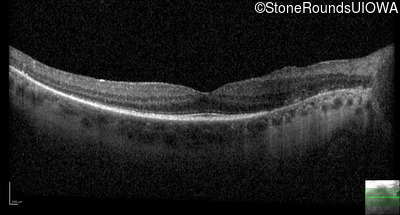

Optical Coherence Tomography - Right - 20/32

Exemplar / OCT Stack